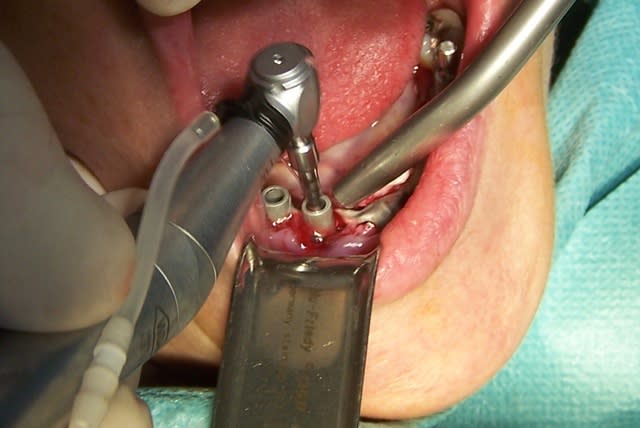

Pour une MCI d'une centrale supérieure tu dois avoir possibilité de mettre au moins du 15 mm de long en raison de la déhiscence vestibulaire qui est pratiquement toujours la règle, tu peux aussi un rien mordre dans le plancher nasal pour assurer le calage primaire. Il te faut prévoir suffisamment large pour la même raison.

Avant d'opérer et d'extraire, il faut préparer les abords immédiats, cureter la granulation sous gingivale des dents voisines, détartrer et surfaçer, vérifier leur vitalité, dénicher toute source potentielle d.infection du site futur, etc.

Il te faut prèvoir de cureter parfaitement après l'extraction, de te munir d'un piézo pour cruanter l'os de partout afin obtenir un beau saignement, de prévoir une membrane biomend B2 par exemple, de 0,5 gr de bio oss en particules de 0,5 à 1 mm.

Quand tu extrais tu vas découper ta dent et l'extraire religieusement pour ne pas briser l'os vestibulaire, tu vas amener ton forêt terminal le plus près possible de ta corticale linguale, laisse de l'espace vide en vestibulaire, tu y mettras du bio oss.

Engage ton implant, finis le vissage à la clé pour bien sentir comment il se visse, veille à orienter correctement l'hexagone éventuel au cas où tu devrais utiliser un pilier angulé, pose ta membrane, fourre le bio oss généreusement, rabbats le tout vers lingual, cruante la membrane au bistouri pour faire passer le pilier définitif ou la vis de cicatrisation haute qui ne doit pas enrouler la membrane sur elle-même !

Quand tu repasseras pour visser à fond le pilier définitif ne le nettoye pas sauf au liquide physiologique pour ne pas tuer les cellules muqueuses ou alors tu prends un nouveau stérile.

Pour la provisoire je prends un pilier provisoire et je construis une dent avec une préforme frasaco et du composite Z250. Le tout hors occlusion vérifié dans tous les mouvements extrêmes mandinbulaires.

Mais sutout j'aurais pratiqué un REMage total préalable de mon patient pour ne pas qu'il ne bruxe pas la nuit.